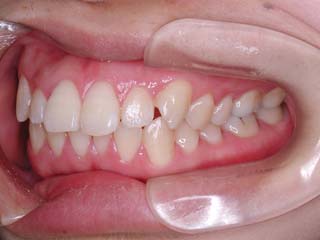

診断名:叢生を伴う上下顎前突

上顎前歯、下顎前歯の前突が見られます。大きな叢生は見られませんが、上下の口唇前突感も伴います。このような不正咬合を上下顎前突と言います。審美的な事もさることながら、歯軸の傾斜の問題から歯にかかるベクトルが良くない事、口唇の筋肉の緊張を強いるような不調和を示す事などから、不正咬合の一つとして考えられています。上顎前突傾向も伴っていますので、積極的に上顎前歯の後退を行う目的で、上顎に固定源となる 目的外使用の オーソアンカー SMAPシステム を装着しました。現在では、歯科矯正用アンカースクリュー(デュアルトップオートスクリュー、ISAアドバンスなど)といった、医療機器認証番号がある製品を用いることが多くなりました。